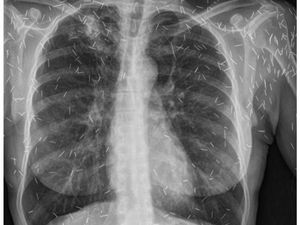

Penampakan Isi Perut Wanita yang Tak Sengaja Telan Sendok Kayu Es Krim

Seorang wanita berusia 21 tahun datang ke UGD rumah sakit. Ia mengaku tidak sengaja menelan sendok kayu saat makan es krim, begini penampakannya.